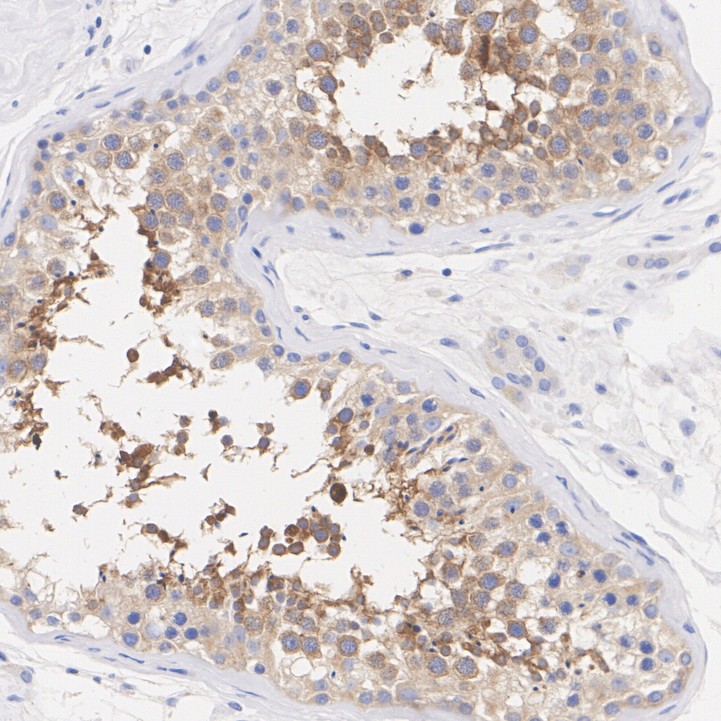

LKB1 Recombinant Rabbit Monoclonal Antibody [PSH09-29] - BSA and Azide free

Catalog# HA751283

IHC-P